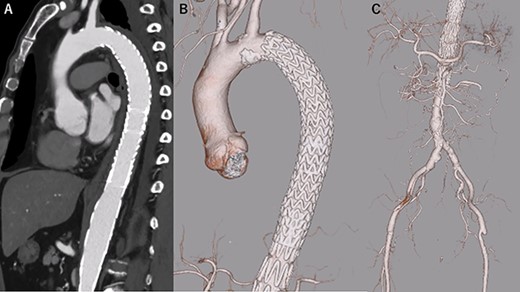

A 68-year-old man developed severe acute back pain and was diagnosed with acute type A aortic dissection with enhanced computed tomography (eCT) in the emergency department of our institute (Fig. 1A and B). The false lumen of the arch and ascending aorta was thrombosed (the maximum short diameter of the ascending aorta was 43.3 mm, the maximum diameter of the false lumen at the ascending aorta was 17.7 mm, Fig. 1C), and the primary entry was placed at the descending aorta. In addition, malperfusions were observed in the right renal artery and both iliac arteries (Fig. 1D). Therefore, we decided to perform TEVAR with the petticoat technique because of the rapid increase in true lumen blood flow.

eCT at diagnosis. (A): Sagittal view, (B) 3D reconstruction of the ascending and descending aorta, (C): Axial view of the ascending aorta and (D): 3D reconstruction of the abdominal aorta and iliac artery.